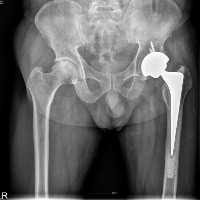

- └ 고관절 골괴사증

고관절 골괴사증